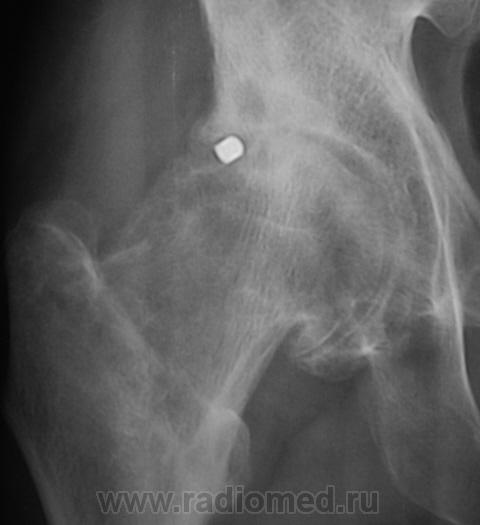

Почему-то на ум пришло сразу "Вот пуля пролетела ,и ага..".

это вероятно и есть состояние после огнестрельного ранения в виде ДОА 3 ст, инородное тело или нет?

Для точной локализации пули нужна попендикулярная ( как в "Двух капитанах" - палочки должны быть попендикулярны) проэкция. Может и не причина артроза?

КТ 2009 года.

Да, Вы правы. Пациент желает "поставить" искусственный сустав.